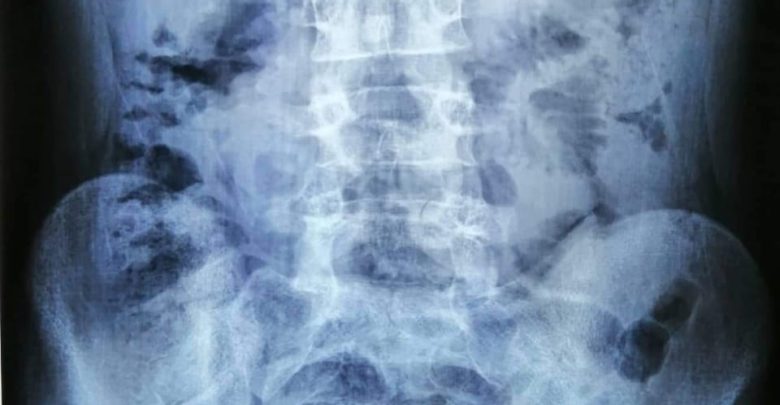

أعلنت مدينة الإمام الحسين ( ع ) الطبية بكربلاء المُقدسة ، إن ” أحد أطبائها الإختصاص ، أنهى وبنجاح معاناة مريض من أهالي محافظة واسط بعمر ( 16) عاماً ، إستمرت نحو ( 10) سنوات ” ، في حين بيَنت إن ” المريض ، غادرها بعد يومين من إجراء العملية ، وهو بصحة جيدة ، وسط ثناء وتقدير ذويه لنجاح العملية وحُسن تعامل الفريق المُعالج معه ” . وبحسب أخصائي جراحة المسالك البولية ، الدكتور أمير الأعرجي ، في حديث لـ ( وكالة كان نيوز ) ، السبت ، إنه ” نجح مؤخراً وبمساعدة فريق طبي وصحي مُتخصص في جراحة الكلى والمسالك البولية ، من إنهاء معاناة شاب من محافظة واسط ، يبلغ من العمر ( ١٦) عاماً ، لازمته منذ أن كان عمره ( 6 ) سنوات ، كونه يعاني من آلام مزمنة في البطن ، مع تقيؤ دائم وفقدان للشهية والوزن وإلتهابات متكررة في المسالك البولية ، والتي دفعت ذويه الى مراجعة العديد من الأطباء في محافظته مراراً ولكن دون جدوى ، مما إضطرهم للمجيء به إلى أطباء محافظة كربلاء المقدسة بحثاً عن حل مشكلته ووضعه الصحي السيء ” ، مبيناً إنه ” عند معاينة المريض ، وإجراء الفحوصات الطبية والمختبرية اللازمة ، تبين لنا ” وجود تضيق في أعلى الحالب الأيسر ، وتحتاج إلى عملية جراحية عاجلة ، وهذا ما حدث ، حيث اُخضع المريض لعملية جراحية وصفها بـ ( المُعَقدة والصعبة ) ، وإستغرقت نحو ( 3 ) ساعات متواصلة ، تمكَنا خلالها من تجميل حوض الكلية اليسرى مع أعلى الحالب الأيسر ” ، لافتاً الى إن ” صعوبة العملية ، تُكمن في إلتفاف الكلية وعدم وجود حوض لها في المكان الطبيعي ” . وأشار الأعرجي ، إن ” الفريق المُساعد له ، كان مؤلفاً من طالب البورد جراحة عامة ، الدكتور مصطفى ثويني ، وأخصائي التخدير الدكتور عادل خضير ، وطالب بورد تخدير ، الدكتور محمد علي ، والملاك الصحي والتمريضي ، الممرضين الجامعيين ، ملحة ذياب و زينب صباح ، وم . طبي حسين خالد ، و . مخدر ضياء عباس ، والممرضين الماهرين ، مؤيد صبيح ، صفا حسين ، فاطمة طالب ، حبيب بدر ” ، مؤكداً إن ” المريض ، غادر المدينة الطبية بعد يومين من إجراء العملية ونجاحها ، وهو بصحة جيدة ، وسط ثناء وتقدير من قبل ذويه لنجاح العملية وحُسن تعامل الفريق المُعالج معه ، متمنين لهم ولبقية زملائهم التوفيق والسداد والنجاح بالعمل خدمةً لمواطني المدينة المُقدسة وزائريها “.